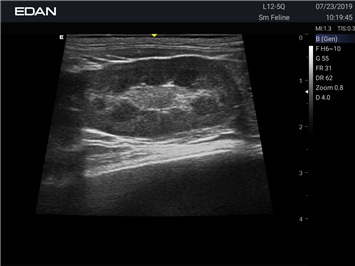

EDAN Acclarix AX2 VET

EDAN Acclarix AX2 VET представляет собой специализированную ветеринарную ультразвуковую систему, сочетающую высокую производительность с доступной ценой. Благодаря продуманной конструкции и передовым технологиям, система обеспечивает качественную диагностику животных различных видов.

• Высокое разрешение для детальной диагностики

• Улучшенная визуализация глубоко расположенных органов